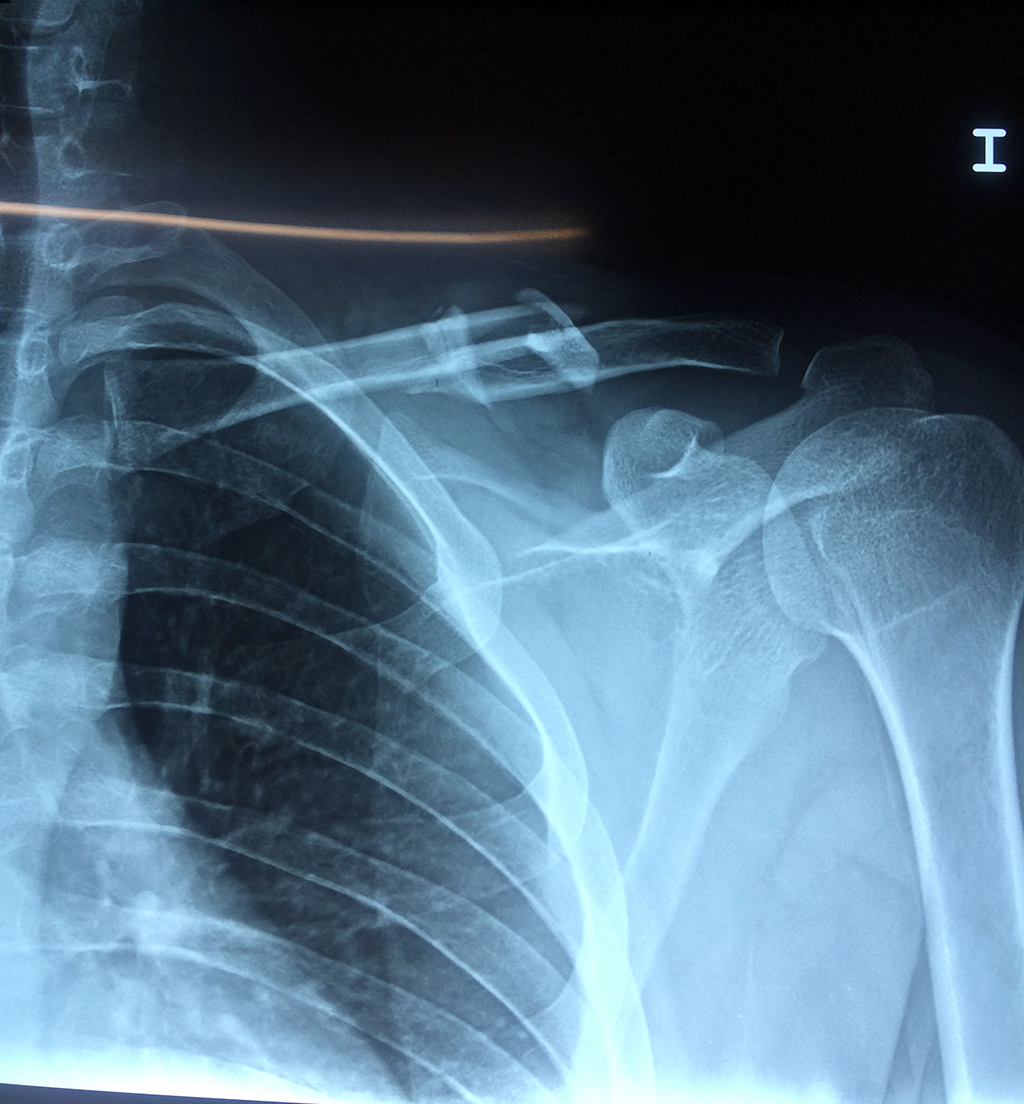

Cirugías de Hombros - Clavícula